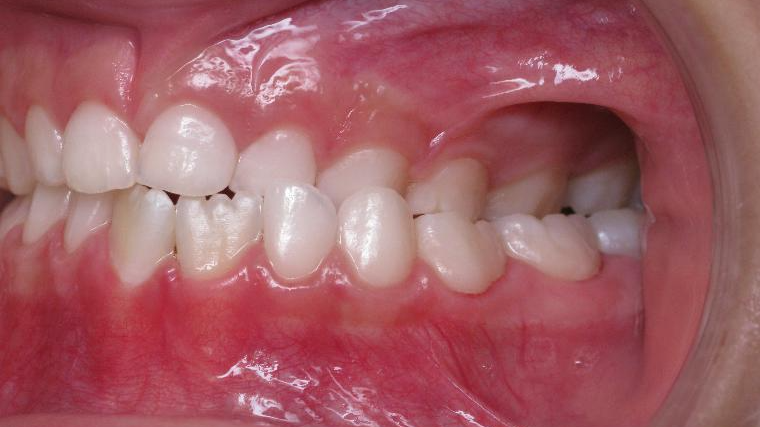

9. inversé gauche 6 ans

inversion des dents posterieur cote gauche

appareillage mobile pendant 9 mois